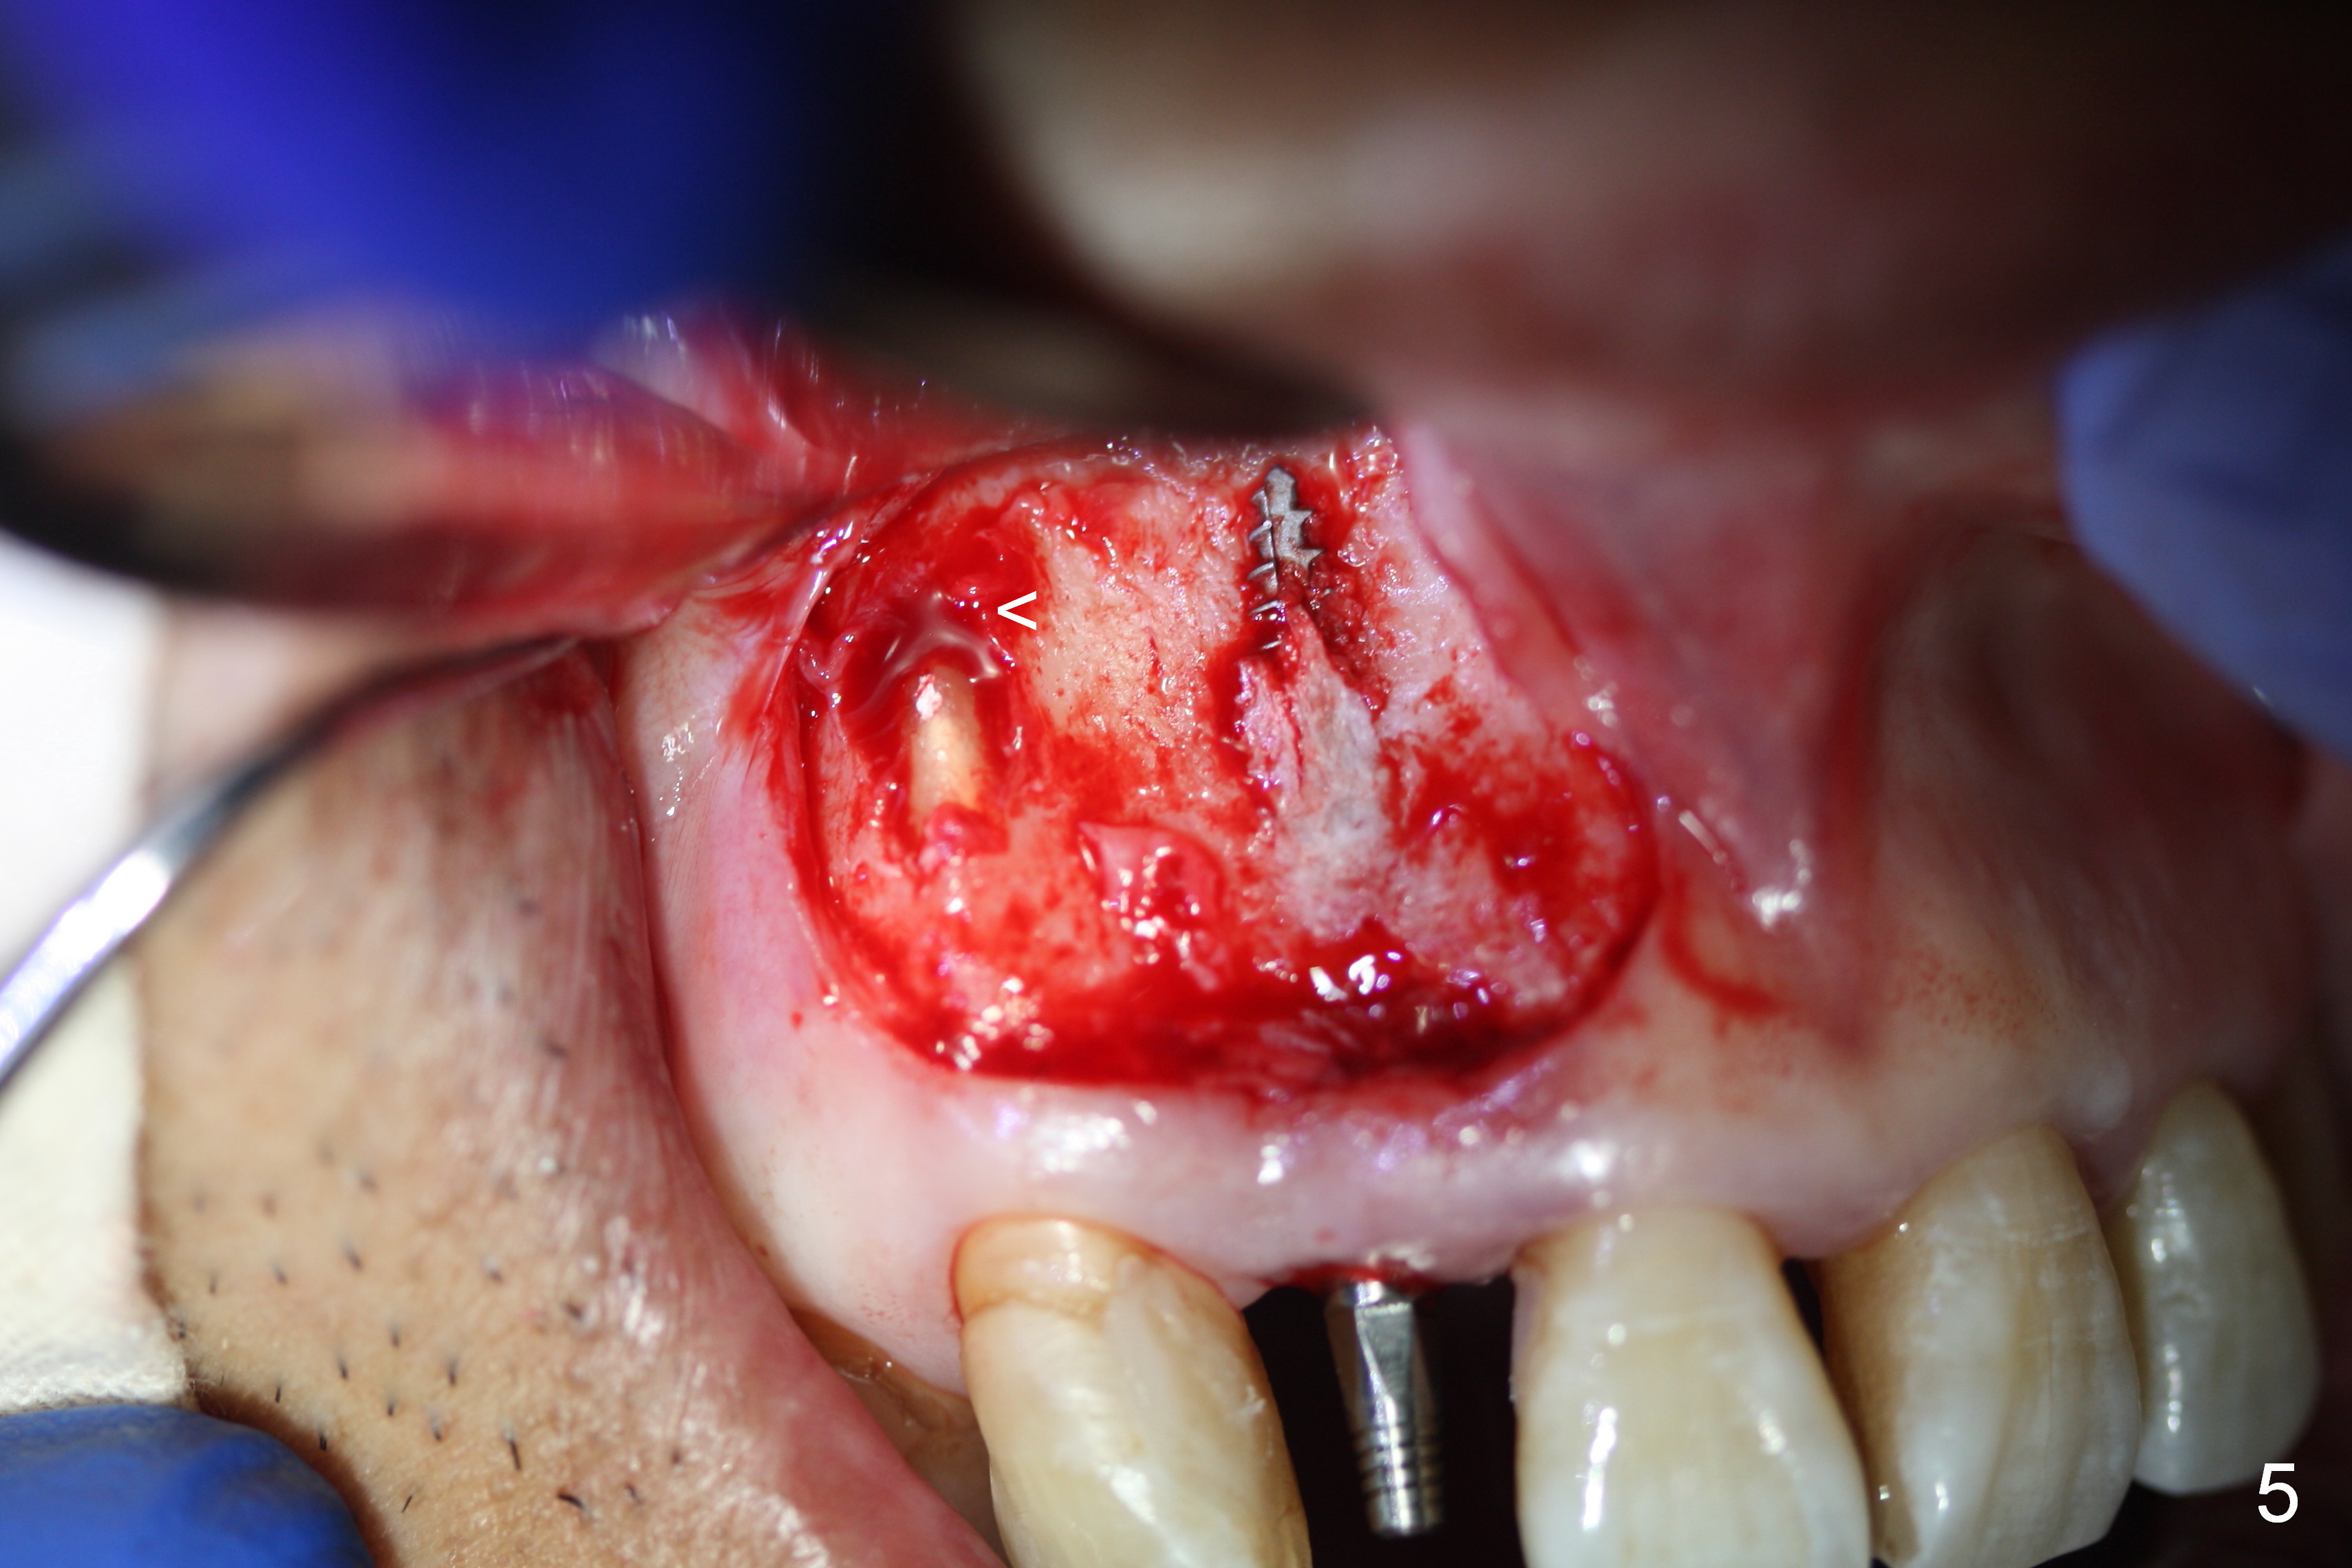

Preop exam shows the apparent wide ridge at #7 (Fig.1). What is ignored preop is the concavity in the apical buccal region (Fig.2 *). When a 3x16(4) mm 1-piece implant is being placed (Fig.3 *, flapless), the apical buccal plate vibration is felt. The biggest mistake is that initial osteotomy is ~ 6 mm shy of the implant length, partially because of 6 mm gingival height. Since the tooth #6 is symptomatic after RCT with paste overfill (Fig.4 >), apicoectomy is contemplated at #6 with exploration of the buccal plate at #7 (Fig.5). Since the implant appears to be long enough, implant apical resection is performed (Fig.6). Since there is coronal thread exposure due to previous periodontitis (Fig.7 <), bone graft is placed in these 3 defective areas after decortication.